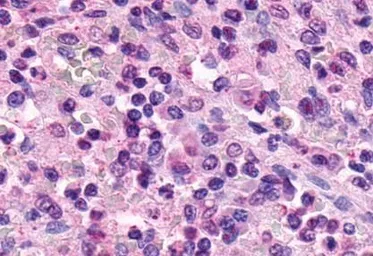

XPR1 antibody

Cat. No. GTX13290

ApplicationsICC/IF IHC-P